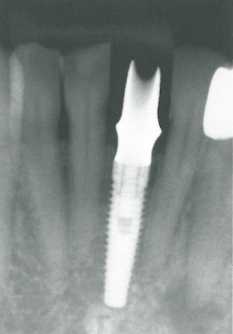

При необходимости хирургический шаблон можно усилить с помощью акриловой пластмассы. На прицельных рентгенограммах представлена последовательность формирования ложа для имплантата точно в заданном положении. Черная линия на шаблоне соответствует направлению одного из трех каналов внутреннего соединения имплантата. Как отмечалось выше, глубина погружения ортопедической платформы имеет очень большое значение для эстетического результата имплантологического лечения. В большинстве случаев платформа должна находиться на 3 мм апикальнее предполагаемого I края десны. В данной ситуации отмечается правильная ориентация со- * единения и оптимальная глубина расположения платформы имплан- 1 тата.

Клиническая и рентгенологическая картина через 1 год и 3 года после заллещения левого центрального резца нижней челюсти с поллощью цельнокераллической коронки с опорой на иллплантат NobelReplace Groovy 3,5 х 13 ллм.